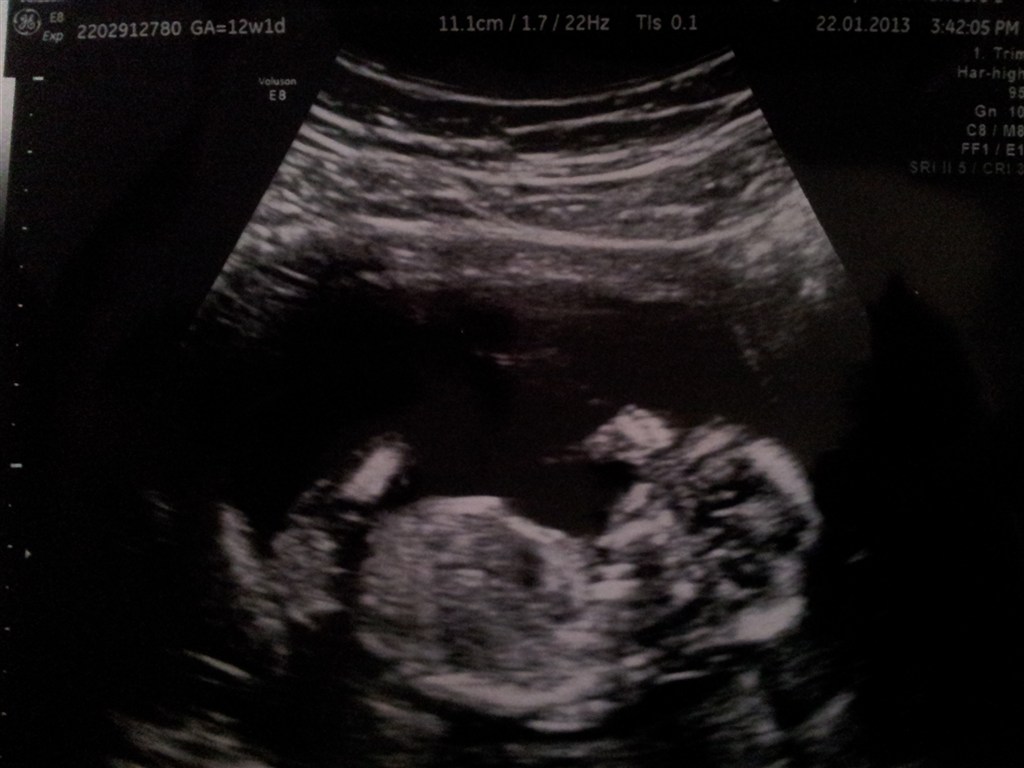

SÅ har jeg været til NF-scanning! Det gik bare helt fantastisk, og vi fik en lav risikovurdering for Downs

Den lille var rigtig livlig og vi fik både hørt hjertelyd, set urinveje, mavesæk, nyrer etc. Det hele var bare top i orden. Det var virkelig en STOR og fantastisk oplevelse!

Jeg blev sat en uge frem, så terminen hedder nu den 28. juli 2013.

På billedet er vores lille guldklump, hvor man også lige kan se dens lille hånd oppe til højre ♥